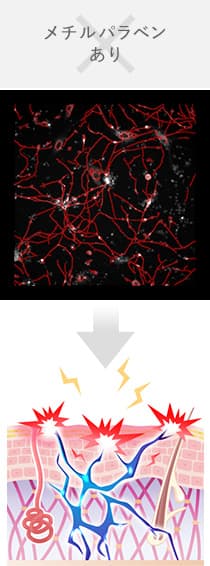

感覚神経に防腐剤を添加すると神経が伸びて、

チクチクやひりひりの原因になりやすくなります。

図1 メチルパラベンによる神経線維の増加